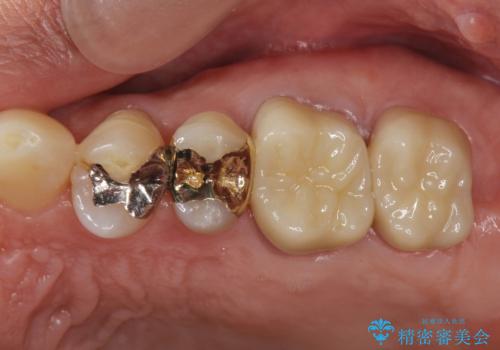

左下の欠損部には強度・表面性状に優れるストローマン社製インプラントを埋入し、合わせて噛み合う上顎の歯もクラウン再補綴による整備を行い安定した咬合関係の構築を目指します。

- 122.1万円(仮歯×5・ストローマンインプラント×2・アバットメント×2・ジルコニアクラウン×5・ゴールドインレー)費用は治療当時の料金となります

今回左下にインプラント治療を行うにあたり、対合する上顎の歯もいっしょに治療を行ったことで安定した咬合関係を構築することができました。